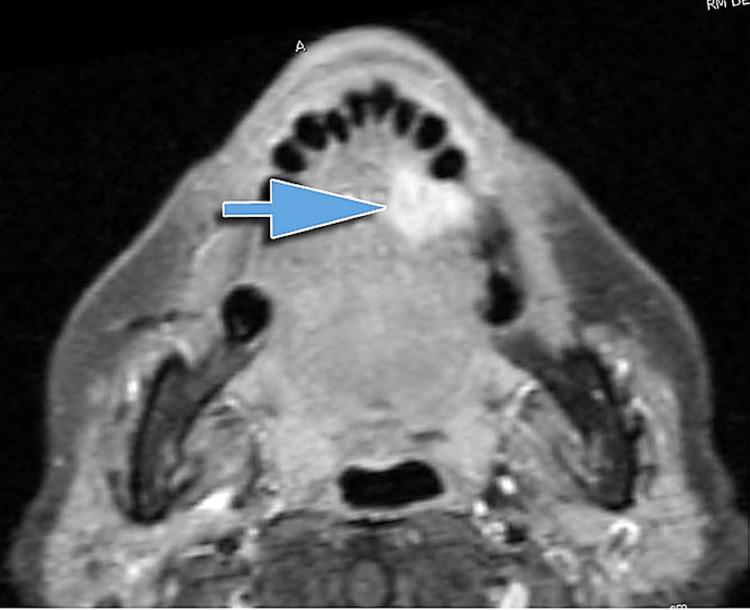

The five osteopathic models recognized by the American Association of Colleges of Osteopathic Medicine guide clinicians in the evaluation and therapeutic choice which must be the most appropriate concerning the patient's needs. Skeletal muscles represent an important interpretation, such as screening and treatment, on which these models are based. A muscle district that is not considered by the usual osteopathic practice is the tongue. The lingual complex has numerous functions, both local and systemic; it can adapt negatively in the presence of pathology, just as it can influence the body system in a non-physiological manner if it is a source of dysfunctions. This paper, the first of its kind in the panorama of scientific literature, briefly reviews the anatomy and neurophysiology of the tongue, trying to highlight the logic and the need to insert this muscle in the context of the five osteopathic models. The clinician's goal is to restore the patient's homeostasis, and we believe that this task is more concrete if the patient is approached after understanding all the contractile districts, including the tongue.

美国整骨医学院协会认可的五种整骨模型指导临床医生进行评估和治疗选择,这些选择必须最符合患者的需求。骨骼肌是这些模型所基于的重要解释内容,例如筛查和治疗。舌部是常规整骨疗法通常不考虑的一个肌肉区域。舌复合体具有众多局部和全身功能;在出现病理情况时它会产生负面适应,同样,如果它是功能障碍的来源,也会以非生理方式影响身体系统。本文是科学文献领域的同类首篇文章,简要回顾了舌部的解剖学和神经生理学,试图突出将这块肌肉纳入五种整骨模型背景下的逻辑和必要性。临床医生的目标是恢复患者的内环境稳定,我们认为,如果在了解包括舌部在内的所有收缩区域后对患者进行治疗,这项任务会更切实可行。